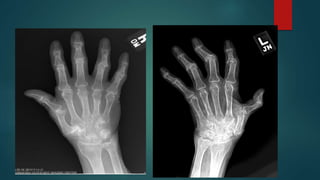

 Erosive osteoarthritis has a predilection for the hands. The

dominant features are those of osteoarthritis, particularly in

terms of distribution:

• distal interphalangeal (DIP) joints

• proximal interphalangeal (PIP) joints

• first carpometacarpal (CMC) joint

 Additional characteristic features include:

• diffuse cartilage loss, with joint space narrowing

• subchondral erosions (at least two central erosions affecting

separate interphalangeal joints); typical central location of the

erosions produces the classic "gull-wing" appearance

• joint ankylosis

• #80 1. Severe joint space narrowing at the first carpometacarpal joint and the interphalangeal joints. At the first carpometacarpal joint there is associated subchondral sclerosis and cyst formation. There are also subchondral central erosions at the heads of the proximal phalanges with marginal osteophytes involving the distal phalangeal bases, demonstrating gull wing deformity through the second and fifth digits. Severe joint space narrowing, subchondral sclerosis, and erosive changes of the scaphoid-trapezium and scaphoid-trapezoid joints. Narrowing of the radiocarpal joint. Diffuse osteopenia. Findings are keeping with erosive osteoarthritic changes 2. Extensive erosive changes and alignment abnormalities are observed along the articular surfaces of the 2nd through 5th PIP and DIP joints bilaterally, as well as at the 1st IP, MCP and carpometacarpal joints bilaterally. These erosive changes assume a gull wing appearance. The alignment abnormalities involving the 1st digits resemble a hitchhiker's thumb. There are no significant erosive changes involving the radiocarpal or intercapral joints, and the 2nd-5th MCP joints are also spared.